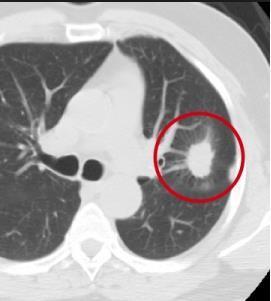

TheproposedsystemismethodicallytestedusingdifferentlungnoduleCTimage.

Fig.1CTscansLungNoduleImages